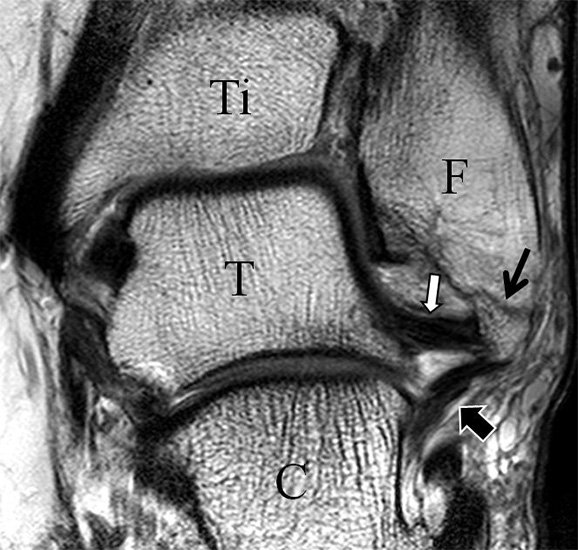

Innenbandapparat

Man unterscheidet bei dem Ligamentum deltoideum eine tiefe Schicht (Pars tibiotalare posterior, Pars tibiotalare anterius) und eine oberflächliche Schicht (Pars tibionaviculare, Pars tibiocalcaneare, Pars tibiotalare posterius superficialis und Tibiospring-Ligament) 10. Hochauflösende Techniken lassen eine differenzierte Beurteilung aller Bandanteile zu. Sowohl rein ligamentäre als auch osteo-ligamentäre Ausrisse sind normalerweise gut zu erkennen. Die Pars tibiotalaris posterior ist multifaszikulär aufgebaut und sowohl axial als auch coronar (Abb. 19 a) gut bildgebend abzugrenzen. Die deutlich kleinere, nur inkonstant angelegte Pars tibiotalare anterior inseriert an einem kleinen Talustuberkel (Abb. 19 b). Ossäre Bandausrisse kommen hier gehäuft vor. Proximal verlaufen die Pars tibiocalcaneare und die Pars tibionaviculare gemeinsam (Abb. 19 c) nach kaudal und trennen sich dann in zum Calcaneus und zum Os naviculare ziehende Bündel auf. Ein besonderer Typ ligamentärer Verbindungen stellt das Tibiospring-Ligament dar. Es verbindet nicht wie für Ligamente typisch zwei Knochen miteinander, sondern es hat seinen ossären Ursprung an der Tibia und inseriert am Pfannenband (Ligamentum calcaneonaviculare plantare, im englischen Schrifttum Spring-Ligament genannt), also nicht ossär. Das Innenband ist mit 60% der Verletzungen am häufigsten betroffen. Isolierte Innenbandverletzungen sind jedoch selten. Sie treten gehäuft assoziiert mit Syndesmosenläsionen, Fibulafrakturen, Verletzungen des Muskulus tibialis posterior und des Pfannenbandes auf (H.-K. Beyer 2003). Entsprechend sollte auf diese Kollateralverletzungen bei der Beurteilung geachtet werden. Eine weitere Folge von Verletzungen des Ligamentum deltoideum ist die chronische Sprunggelenksinstabilität. Arthroskopisch weisen hier bis zu 40% der Patienten einen elongierten Verlauf des Ligamentum deltoideum auf. In diesem Patientenkollektiv besteht auch eine erhöhte chondrale Komorbidität mit arthroskopisch erkennbaren Knorpelschäden (98%) im Gegensatz zu der Patientengruppe (66% Knorpelschäden) mit reiner Außenbandinstabilität 11. Dies belegt die klinische Bedeutung von Innenbandverletzungen.